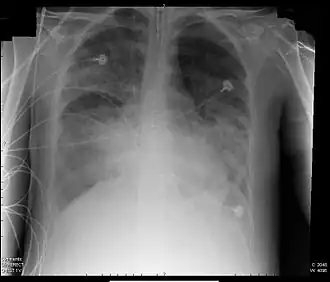

Röntgenfoto van een patiënt met ARDS

ARDS ontstaat op nog onbekende wijze ten gevolge van een ernstige ziekte van de longen zelf (bijvoorbeeld een longontsteking), of een ziekte elders in het lichaam. Door de ontstekingsreactie treden vocht, eiwitten en ontstekingscellen uit de longbloedvaten in het longweefsel. Hierdoor wordt de overdracht van zuurstof vanuit de longen naar het bloed bemoeilijkt, waardoor een tekort aan zuurstof in het bloed (hypoxemie) ontstaat. Op een röntgenfoto van de longen zijn in beide longen zogenoemde consolidaties te zien: opeenhopingen van vocht, cellen en afvalmateriaal.